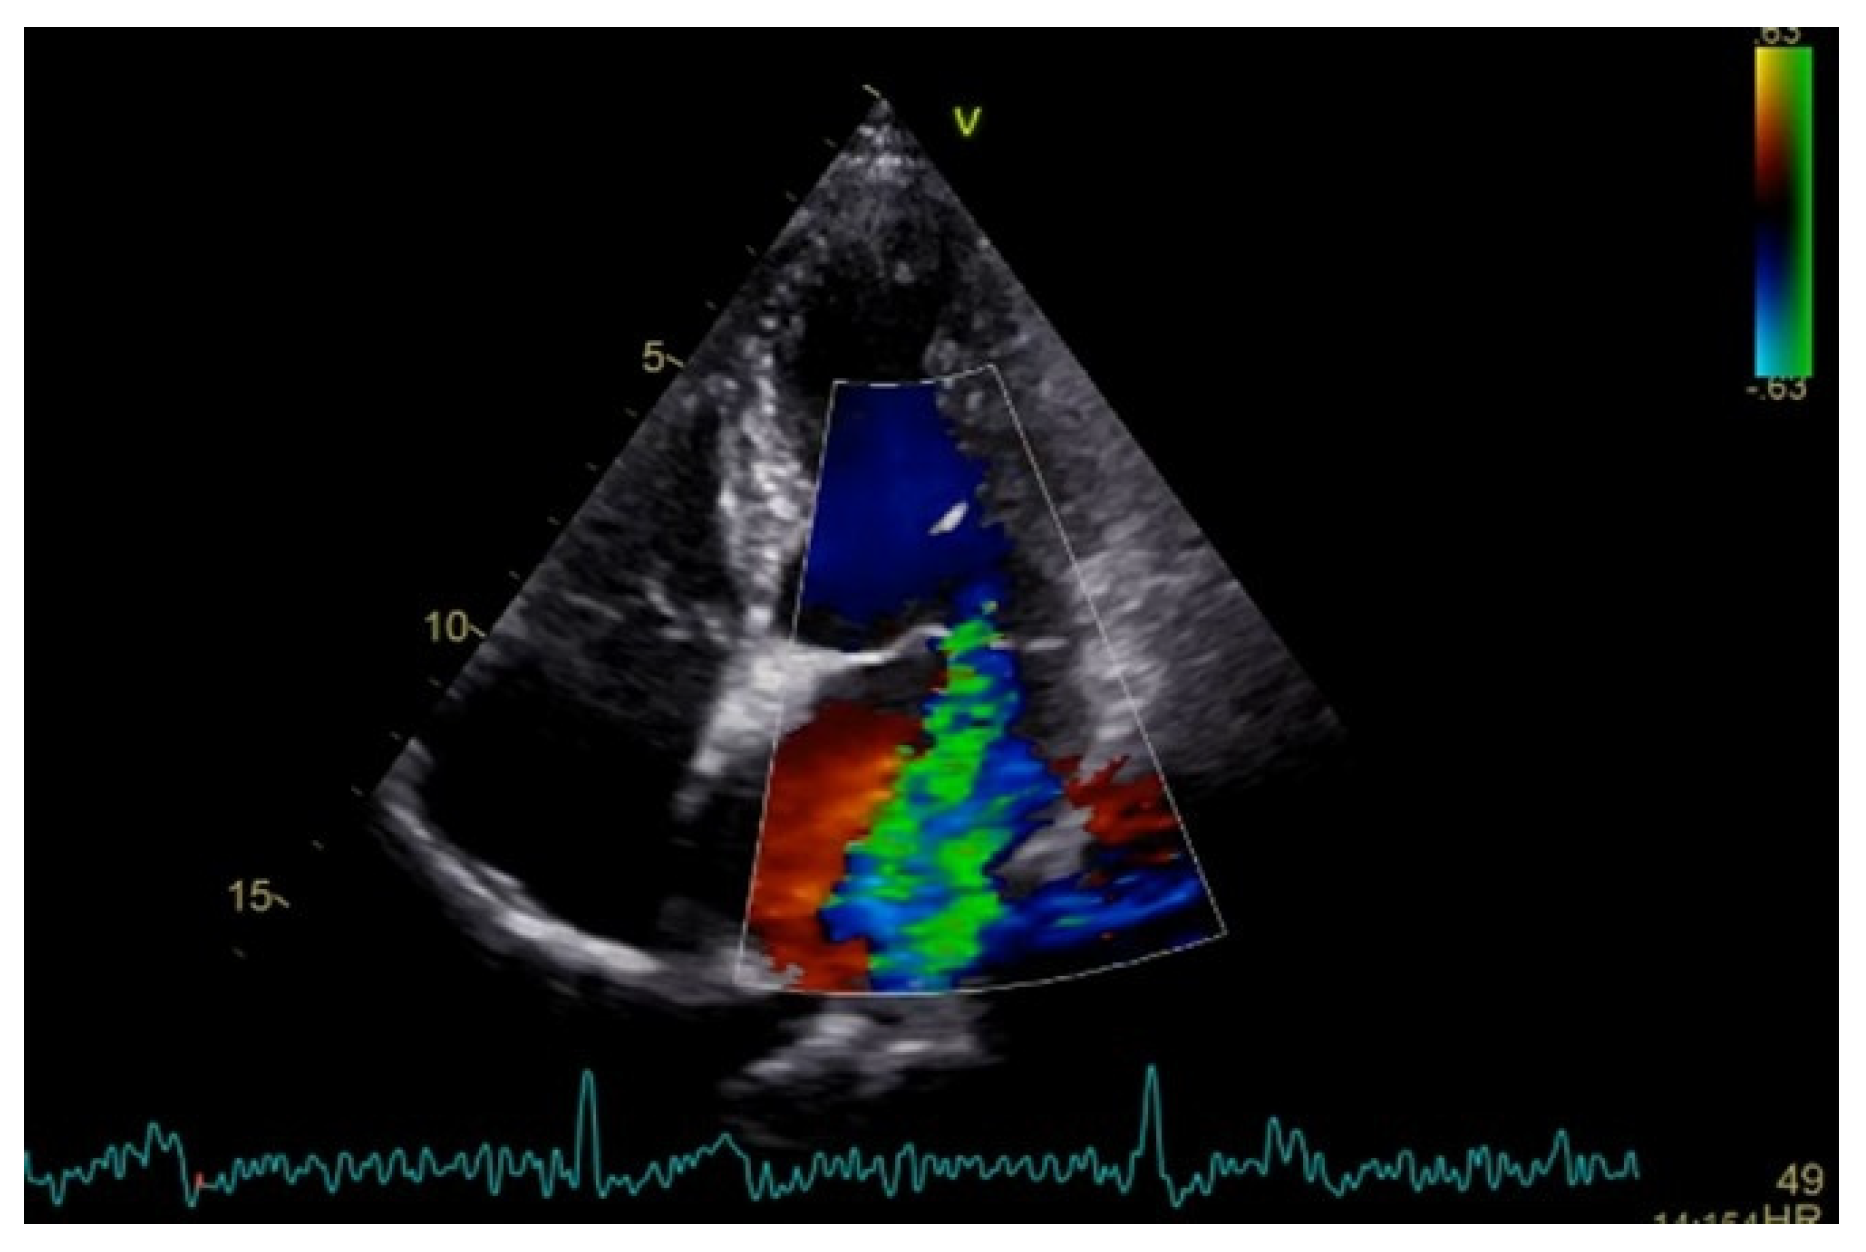

Severe mitral regurgitation was identified, manifested by an eccentric regurgitant jet and associated left atrial dilatation (Figure 4). Moderate tricuspid regurgitation with right atrial dilatation was also present. Both the left and right ventricles were of normal size and function. Global longitudinal strain was preserved for both ventricles, with an average of −22.9% for the left ventricle and −22.0% for the right ventricle, although a mild degree of dispersion in longitudinal strain peaks was observed (Figure 5).

Apical four chamber view showing severe mitral regurgitation with left atrial dilatation.